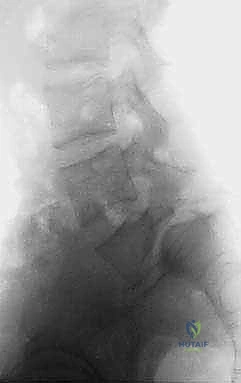

2. المفصل القطني العجزي (L5-S1)

هذا المفصل هو نقطة التقاء آخر فقرة في العمود الفقري القطني (L5) مع أول فقرة ملتحمة في عظم العجز (S1). هذا الموقع هو الأكثر عرضة للانزلاق الفقاري على الإطلاق. لماذا؟ لأن هذا المفصل يتحمل الجزء الأكبر من وزن الجزء العلوي من الجسم، بالإضافة إلى أنه يقع في نقطة انتقال منحنى العمود الفقري، مما يجعله عرضة لضغوط ميكانيكية هائلة (قوى القص).

في الحالات المزمنة، وبسبب الاحتكاك المستمر، يمكن أن يتغير شكل العظام؛ حيث يصبح السطح العلوي للعجز (S1) على شكل قبة أو محدباً، بينما يصبح السطح السفلي للفقرة (L5) مقعراً، وقد يبرز عند زاويته الأمامية السفلية، مما يزيد من تعقيد الحالة.

3. جذور الأعصاب (Nerve Roots)

مع انزلاق الفقرة إلى الأمام، تضيق الفتحات (الثقوب الفقرية) التي تخرج منها جذور الأعصاب. في حالة انزلاق L5-S1، غالباً ما تكون جذور الأعصاب القطنية الخامسة (L5) مشدودة بإحكام فوق "قبة" العجز، مما يؤدي إلى تهيج العصب، والتهابه، وظهور آلام مبرحة تمتد على طول الساق.

هي الخطوة الأولى والأساسية. يتم التقاط صور للعمود الفقري من عدة زوايا (أمامية، جانبية، ومائلة). الأشعة الجانبية هي الأهم لتحديد درجة الانزلاق (حسب تصنيف مايردينغ). كما يتم إجراء أشعة ديناميكية (أثناء الانحناء للأمام وللخلف) لتقييم مدى "عدم الاستقرار" (Instability) وحركة الفقرة أثناء الحركة. -